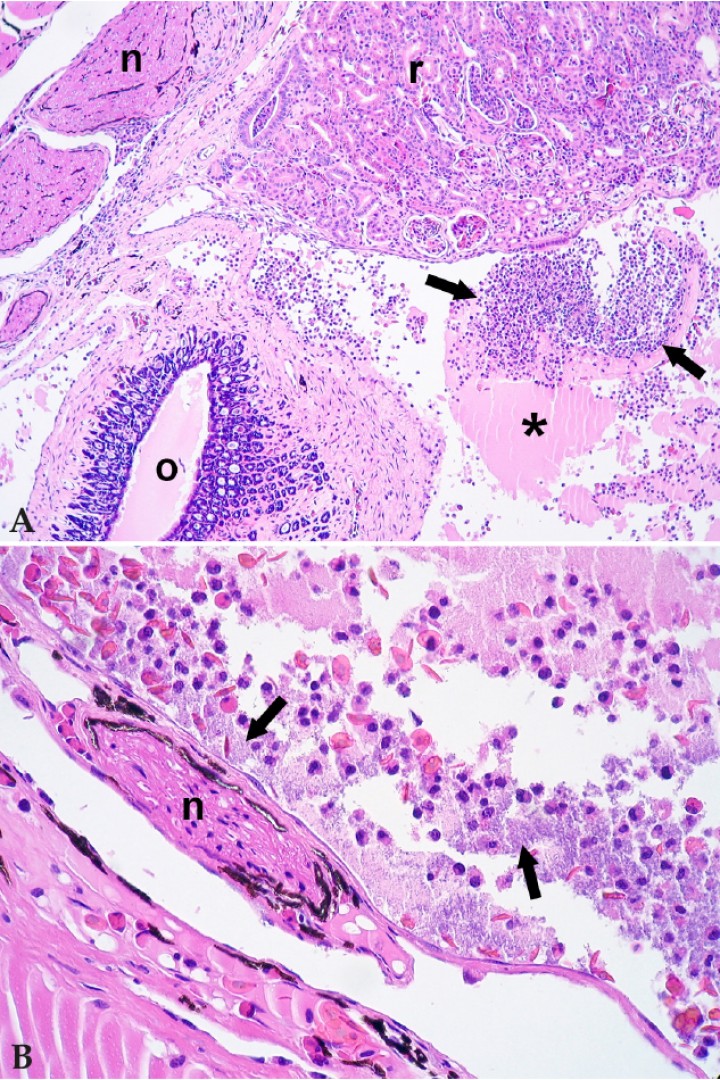

Se observaron 11 casos de celomitis bacteriana, en los que se contabilizaron 5 anfibios con micobacteriosis y 5 con celomitis supurativas y/o fibrinosas caracterizadas por acumulación de exudado abundante en la cavidad celómica (Fig. 3) como principal proceso de enfermedad o asociadas a otras lesiones inflamatorias, particularmente nefritis. El caso restante consistía en una bacteriemia intensa con celomitis leve y acumulación de líquido proteico en la cavidad celómica de una rana junco arborícola africana (Hyperolius concolor). No se dispone de aislamiento bacteriano de estos casos.

<p>(<strong>A</strong>) Cavidad celómica; rana dardo verdinegra (<em>Dendrobates auratus</em>). La cavidad celómica contiene exudado con material proteico (asterisco) y células inflamatorias (flechas); n: nervio, r: riñón, o: oviducto. Hematoxilina-eosina, x100. (<strong>B</strong>) Cavidad celómica; rana dardo verdinegra (<em>Dendrobates auratus</em>). Detalle del exudado de la cavidad celómica, con granulocitos, eritrocitos, material proteináceo y bacterias (flechas); n: nervio. Hematoxilina-eosina, x400.</p>

(A) Cavidad celómica; rana dardo verdinegra (Dendrobates auratus). La cavidad celómica contiene exudado con material proteico (asterisco) y células inflamatorias (flechas); n: nervio, r: riñón, o: oviducto. Hematoxilina-eosina, x100. (B) Cavidad celómica; rana dardo verdinegra (Dendrobates auratus). Detalle del exudado de la cavidad celómica, con granulocitos, eritrocitos, material proteináceo y bacterias (flechas); n: nervio. Hematoxilina-eosina, x400.